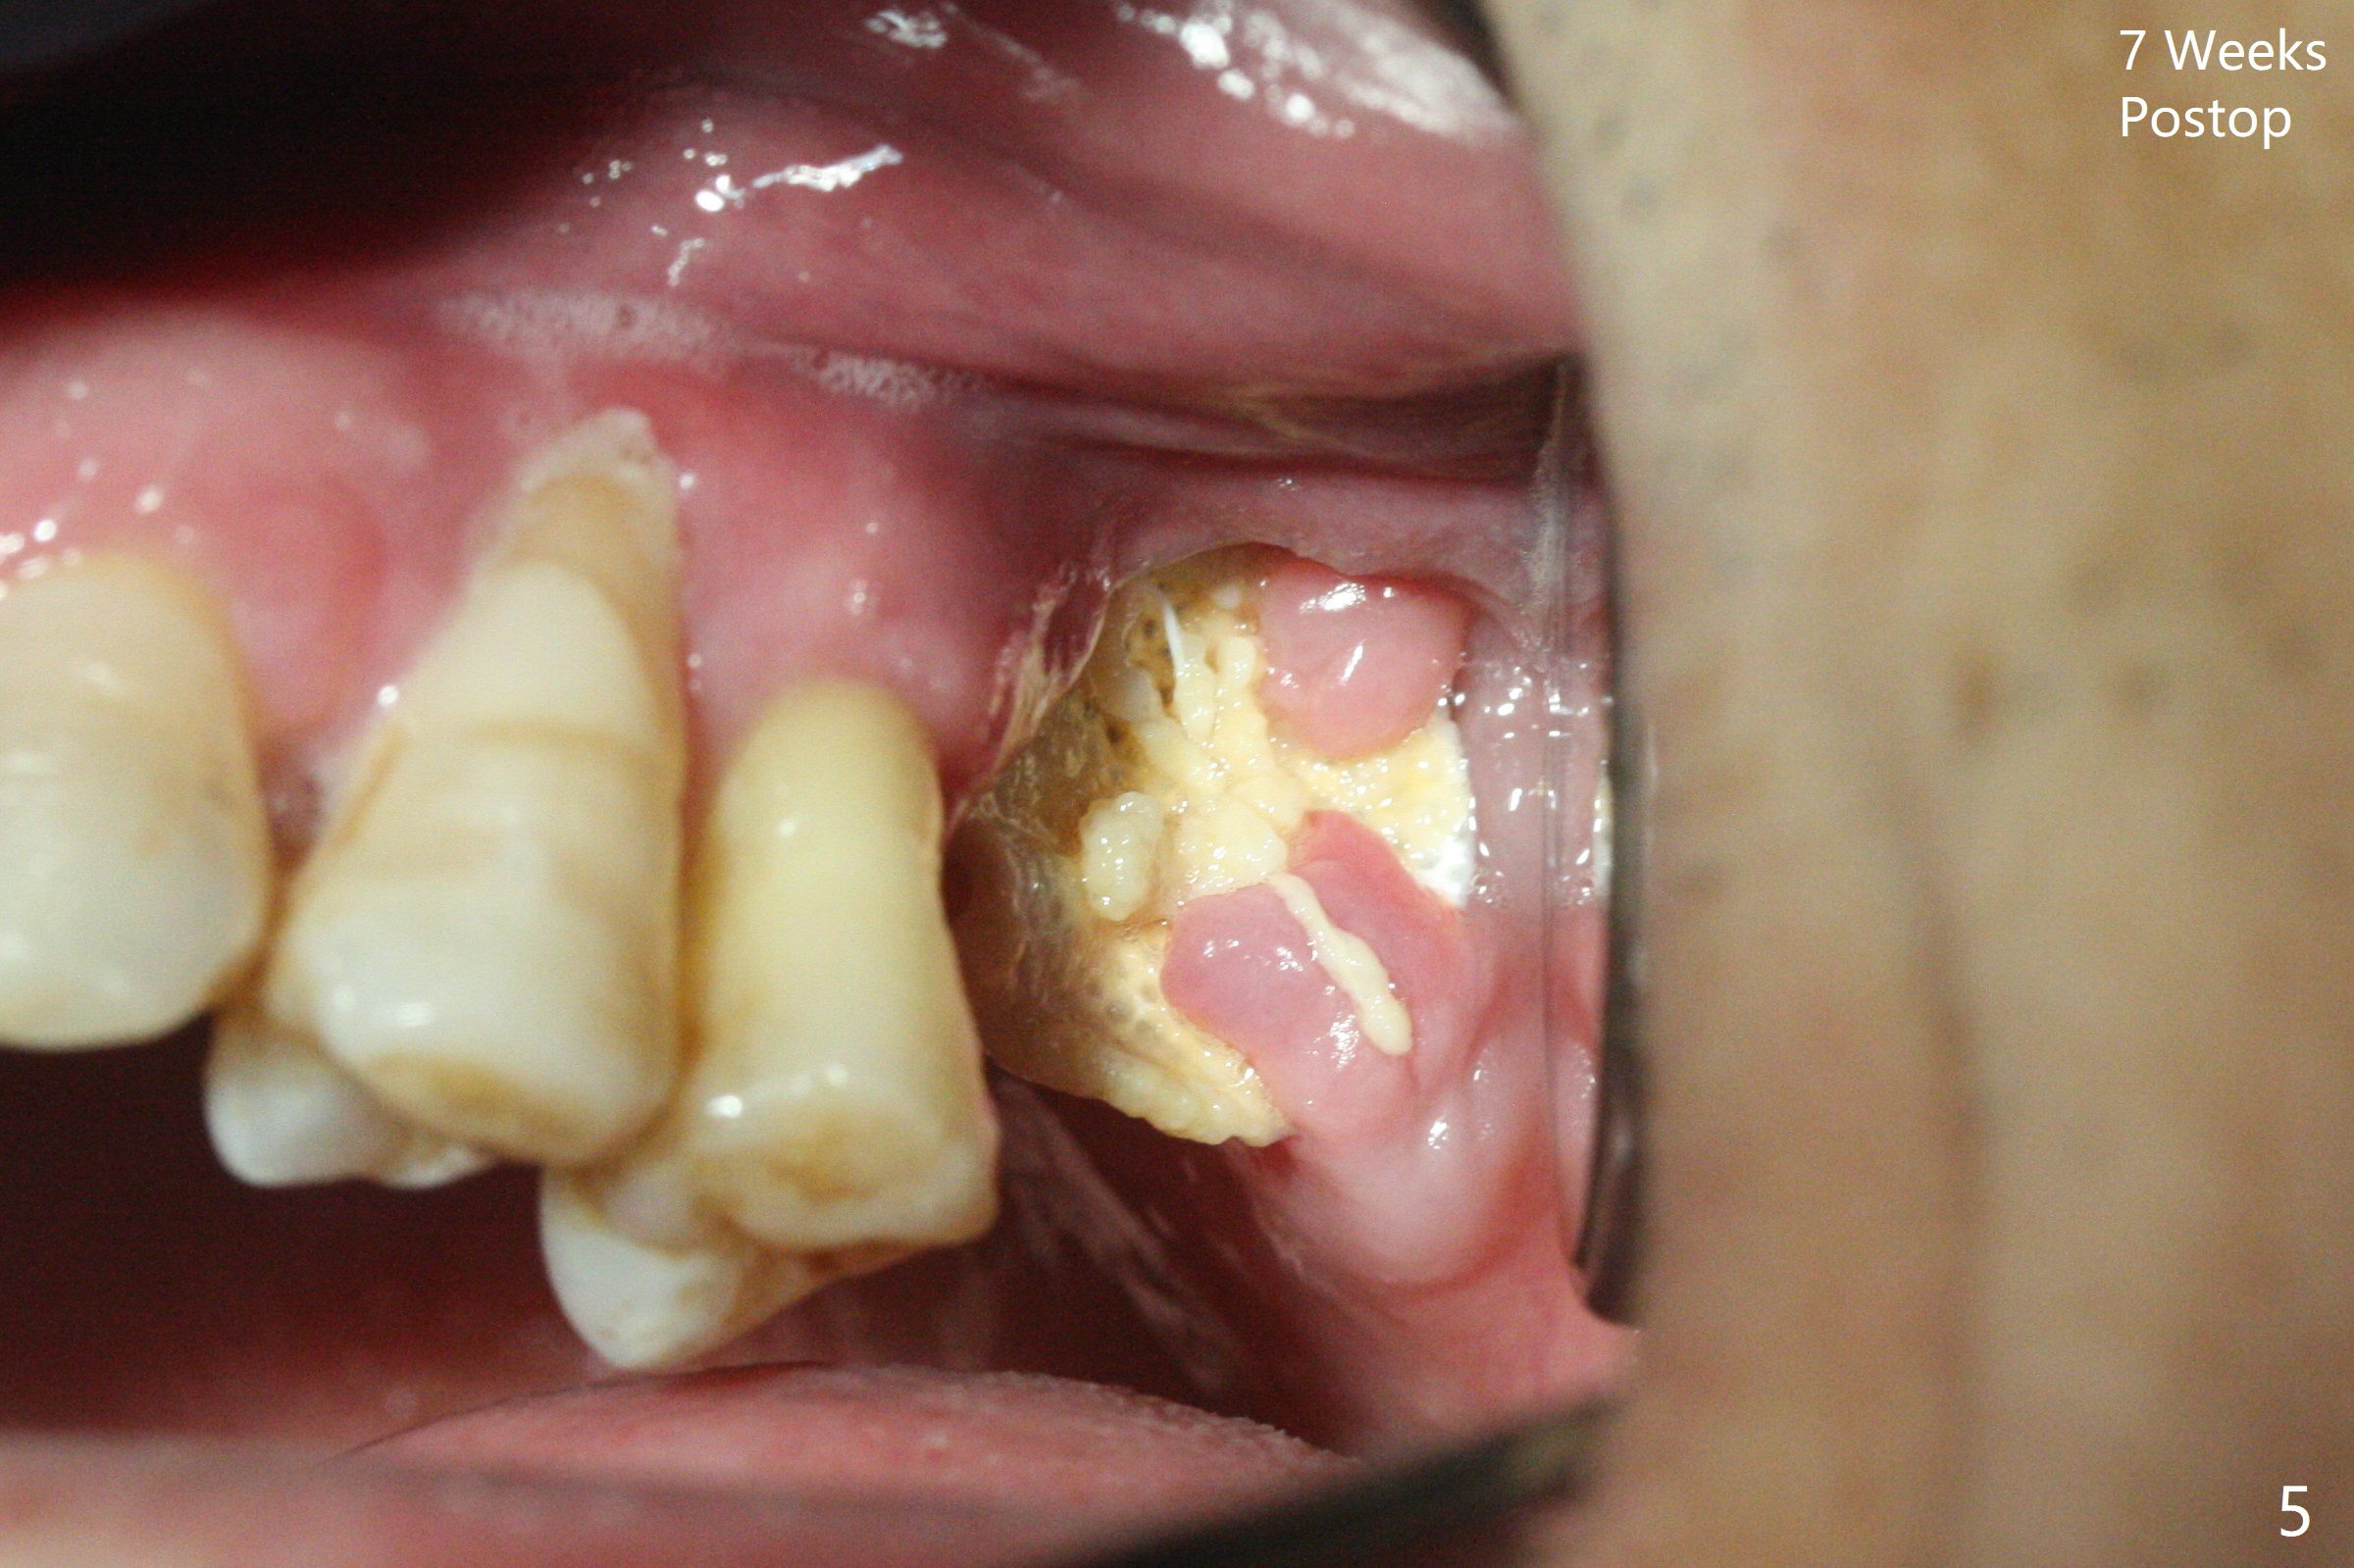

47岁男原本回诊所拔除近中左上智齿(16号牙),影响第一磨牙(14号牙)植牙周围炎治疗后卫生维护。事先制备PRF(图一,二)和骨块(图三 *),拔牙顺利,发现植牙螺纹依然暴露,决定取出植体,上颌窦底板缺失,但膜仿佛完整,放置一小块PRF于上颌窦底,促进上颌窦膜愈合,然后加入新的骨粉,与剩余上清液(图三 >)调袢,虽然不再形成粘性骨块,但是还有好处,放置于拔牙窝以及植牙窝(图四 *),浅部放置骨块(S),这样骨粉不容易丢失,表面再放置PRF膜和不可吸收膜(Cytoplast),使用PTFE缝线。术后7周Cytoplast几乎完全暴露(图五)。当它取出后,骨粉好像损失不少(图六)。二个月后再评价。术后6.5月第一磨牙区仍萎缩(图七),只好再植骨,在第三磨牙区安置一个tenting screw,也在第一磨牙区植入第二个钉子,但是不牢靠,因为仍处于纤维状,把它往上颌窦推作为上颌窦粘膜(图八:>),然后提升(*)。在第一,第三磨牙交界处打入第二个帐篷钉,在两个钉子周围放置粘性骨粉,覆盖PRF膜,缝合。估计植骨效果不佳,植牙时再植骨。